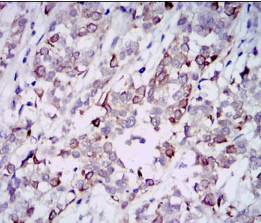

GAB1 Mouse Monoclonal antibody[1A7C1]

IHC    1/200 - 1/1000